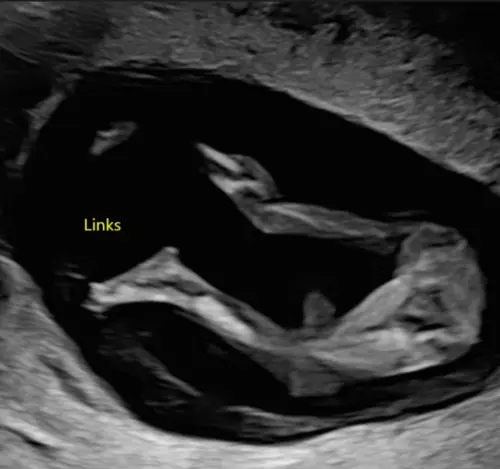

Meisje

Door die twee streepjes, toch? Chatgpt zegt dat het een uitsteeksel is, en zegt vermoedelijk een jongen, dus ik twijfel enorm, maar mij lijkt het ook een meisje. Dankjewel voor het meekijken.

Ja vermoed ik wel, anders zou je daar balletjes moeten zien met 18 weken. Voor het mooie moet het beeld iets meer naar voren zijn, maar chatgpt heeft het vaker fout dan goed🤣

Dit is zeker een meisje hihi